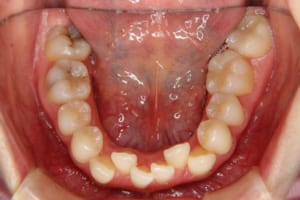

治療前

治療後

主訴 下の歯の凸凹

治療期間 4年6か月

抜歯および非抜歯 上顎:右側中切歯、右側側切歯、左側第一小臼歯

下顎:両側第一小臼歯